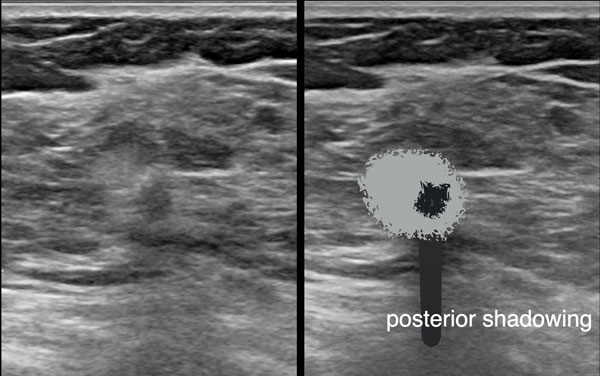

- Bóng cản âm phía sau

Tổn thương bên phải là u xơ tuyến vú.

- Hình bầu dục với múi nhẹ

- Bờ rõ nét

- Hướng nằm ngang, song song với da

- Tăng âm phía sau

Phía sau hoặc sâu hơn so với xương sườn, không thể tạo hình ảnh do sóng âm bị hấp thụ, tạo ra một xảo ảnh gọi là bóng cản âm phía sau.

Điều này có nghĩa là không thể quan sát được cấu trúc phía sau xương sườn, và vùng phía sau xương sườn trên hình ảnh sẽ có màu đen.